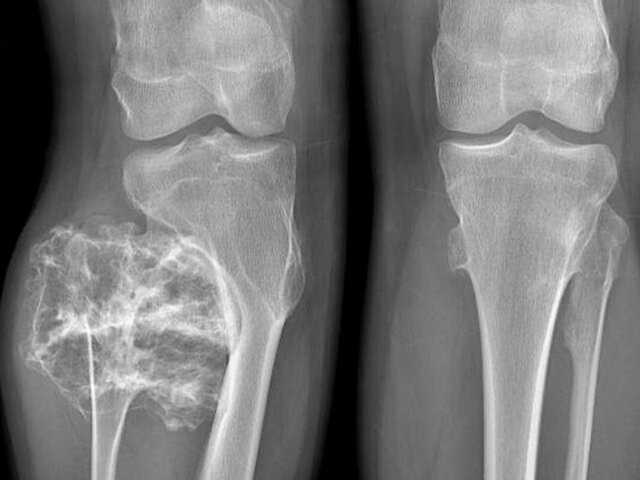

Фото: mz.mosreg.ru

Врачи Московской областной детской клинической травматолого-ортопедической больницы удалили 15-летнему подростку опухоль в ноге размером 9 сантиметров, сообщает телеканал "360" со ссылкой на пресс-службу министерства здравоохранения Подмосковья.

У подростка выявили твердое новообразование в области малоберцовой кости. Обследование показало, что это остеохондрома – образование, покрытое хрящевой "шапочкой", которое часто возникает в детском и подростковом возрасте.

Как пояснил травматолог Сергей Хохлов, подобные опухоли нередко выявляют случайно из-за отсутствия боли и дискомфорта.

"К сожалению, у данного заболевания не бывает обратного развития и единственный метод лечения – хирургический. В ходе операции мы успешно удалили опухолевидное образование в пределах здоровой костной ткани", – поделился врач.

Пациента уже выписали домой для дальнейшего амбулаторного наблюдения. Хирургам удалось сохранить полную функцию ноги. Ожидается, что через три недели подросток сможет вернуться к обычному образу жизни.